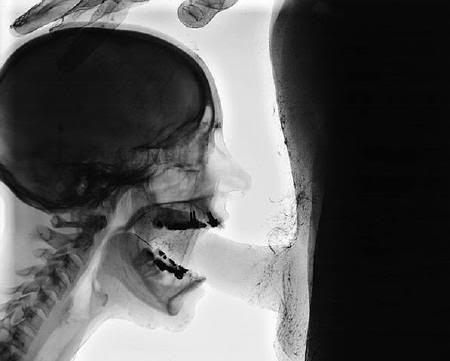

http://images.google.ru/imgres?imgurl=http://prikolka.ru/Muzei/Image/R_11.jpg&imgrefurl=http://prikolka.ru/Muzei/Rengen_Foto9.html&h=395&w=500&sz=29&tbnid=iWo_j48wB7YJ:&tbnh=100&tbnw=127&hl=ru&start=48&prev=/images%3Fq%3D%25D0%25B2%25D0%25BB%25D0%25B0%25D0%25B3%25D0%25B0%25D0%25BB%25D0%25B8%25D1%2589%25D0%25B5%26start%3D40%26svnum%3D10%26hl%3Dru%26lr%3D%26sa%3DN

Заметно повеселел.